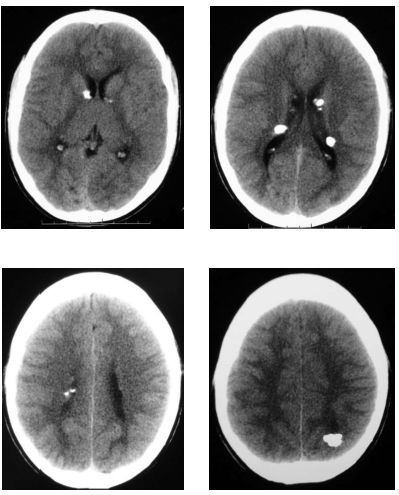

Em relação à patologia desse paciente, julgue o item a seguir.

As calcificações subependimárias devem corresponder a hamartomas, os quais são encontrados em 95% dos portadores dessa entidade.

O diagnóstico mais provável é de esclerose tuberosa, sendo a ressonância magnética de encéfalo indicada para pesquisa de hamartomas corticais, cuja demonstração é limitada na tomografia computadorizada.

Paciente com 11 anos de idade, do sexo masculino, apresenta moderada deficiência intelectual e crises convulsivas, além de lesões cutâneas do tipo adenoma sebáceo, sem outras queixas ou outras patologias conhecidas. Realizou uma tomografia computadorizada cujas imagens são mostradas a seguir.

A tríade clássica de apresentação clínica de retardo mental, convulsões e adenoma sebáceo está presente em mais de 90% dos pacientes portadores da patologia em questão, sendo os métodos de imagens necessários apenas para a avaliação das complicações.